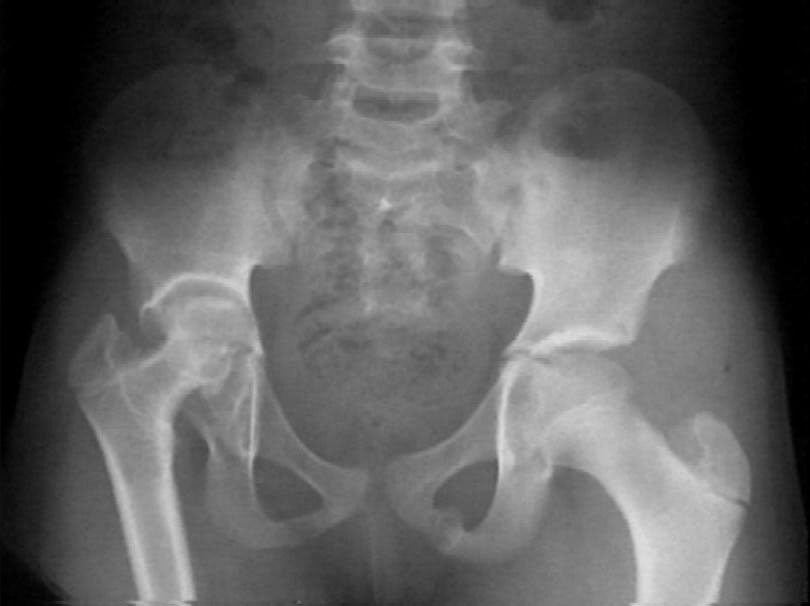

History: A 10 year old black female complains of pain in the right hip. There is no history of fever.

Physical Exam : Good general condition.

Rt Hip : Trendelenberg positive. Wasting of the gluteal muscles. All movements of the hip are limited.

Initial xray - Click to enlarge.

Lab: Leukocytes - 7300/cubic mm, ESR - 10 mm/hr., Sickle cell - negative, IDR(PPD) - 10 mm with a mark of old BCG vacccination.